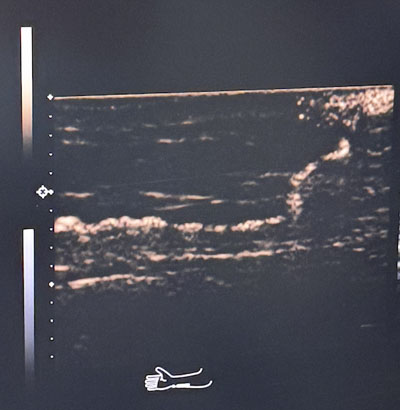

術前超聲造影